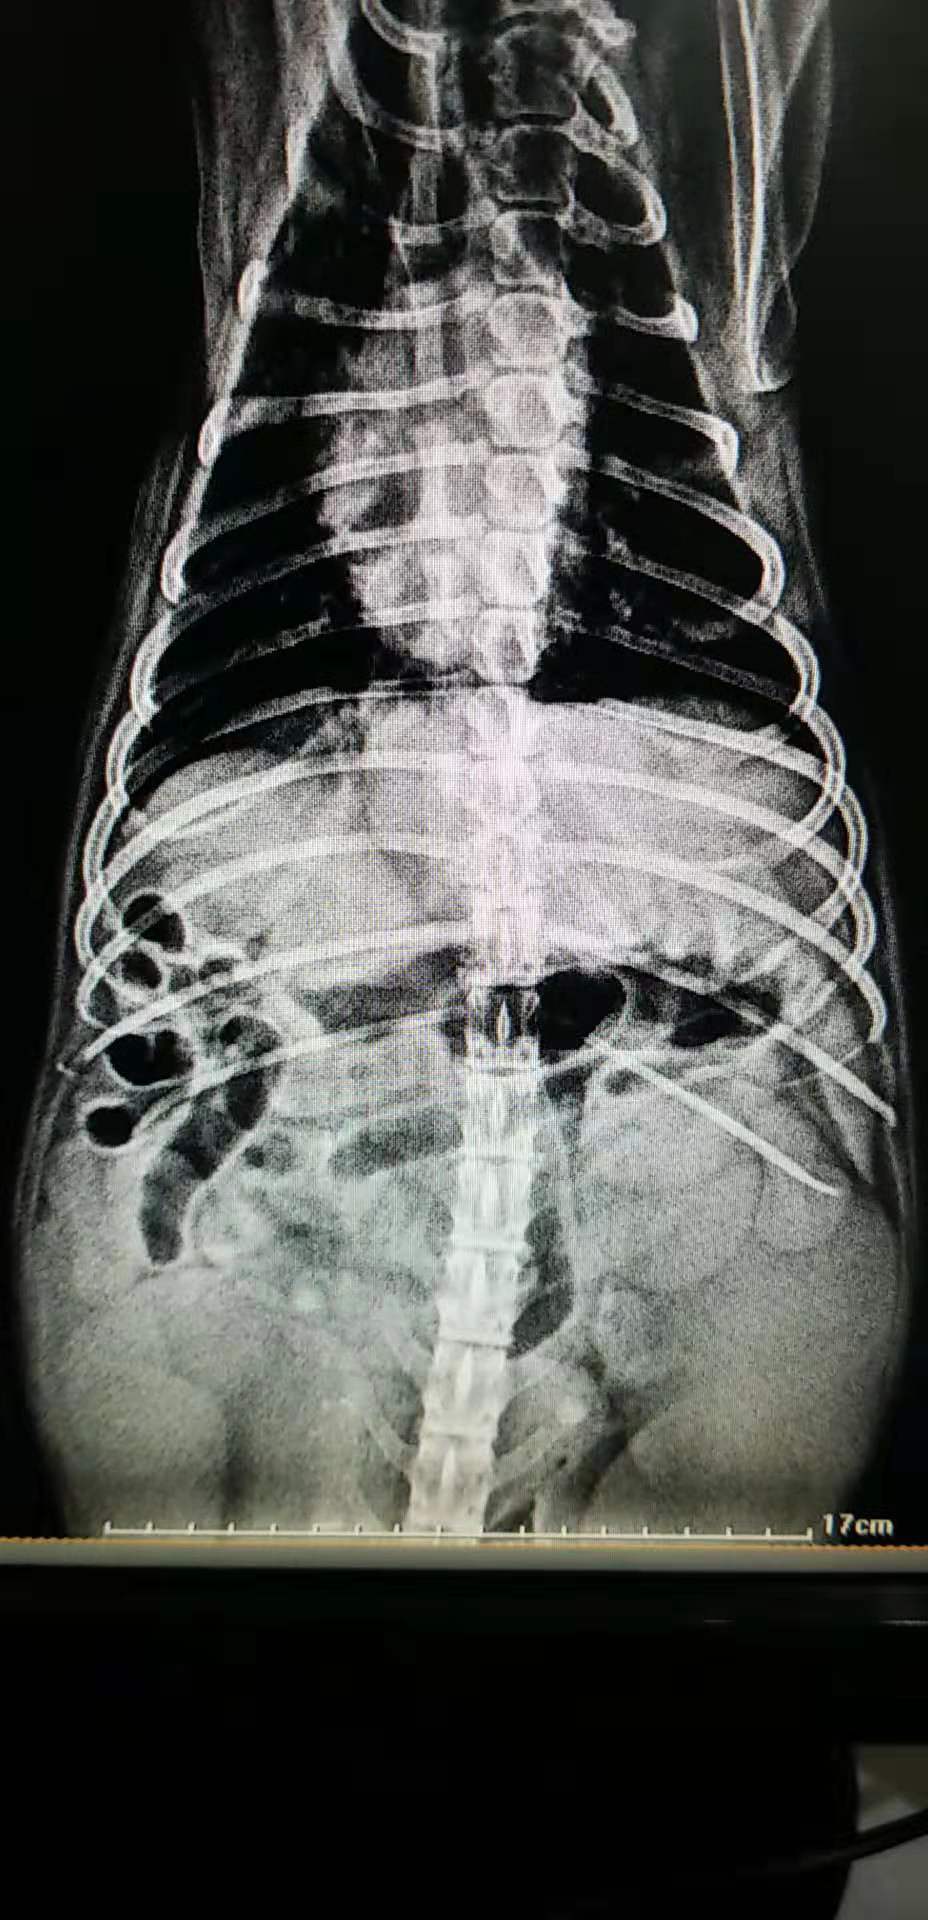

X光的摄片

一例犬的子宫蓄脓病例